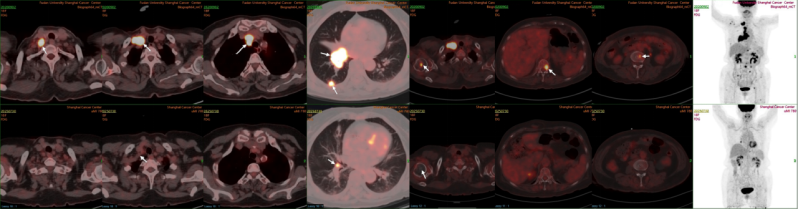

原发灶胸部CT结果对比图(基线、2周期后、4周期后、6周期后)

2、患者2025-07-30复查PET/CT:对比前片:右下肺MT治疗后,右肺病灶较前退缩,仅局部FDG代谢增高,密切随访;右侧肺门、纵隔、锁骨上转移淋巴结较前明显退缩,右肺内转移灶较前消退,全身多发骨转移较前好转,右侧胸膜转移较前消退,均未见FDG代谢增高。疗效评估为持续PR。

image.png

PET-CT结果对比图(基线、2025-07-30)